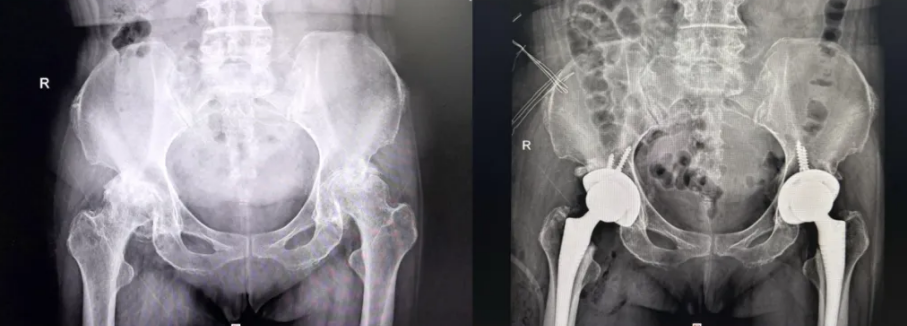

张奶奶患股骨头坏死晚期,年初时在该科完成了左侧髋关节置换术,左侧术后疼痛缓解明显,此次通过右侧手术解决另一侧病变问题。

(▲张奶奶术前术后影像)